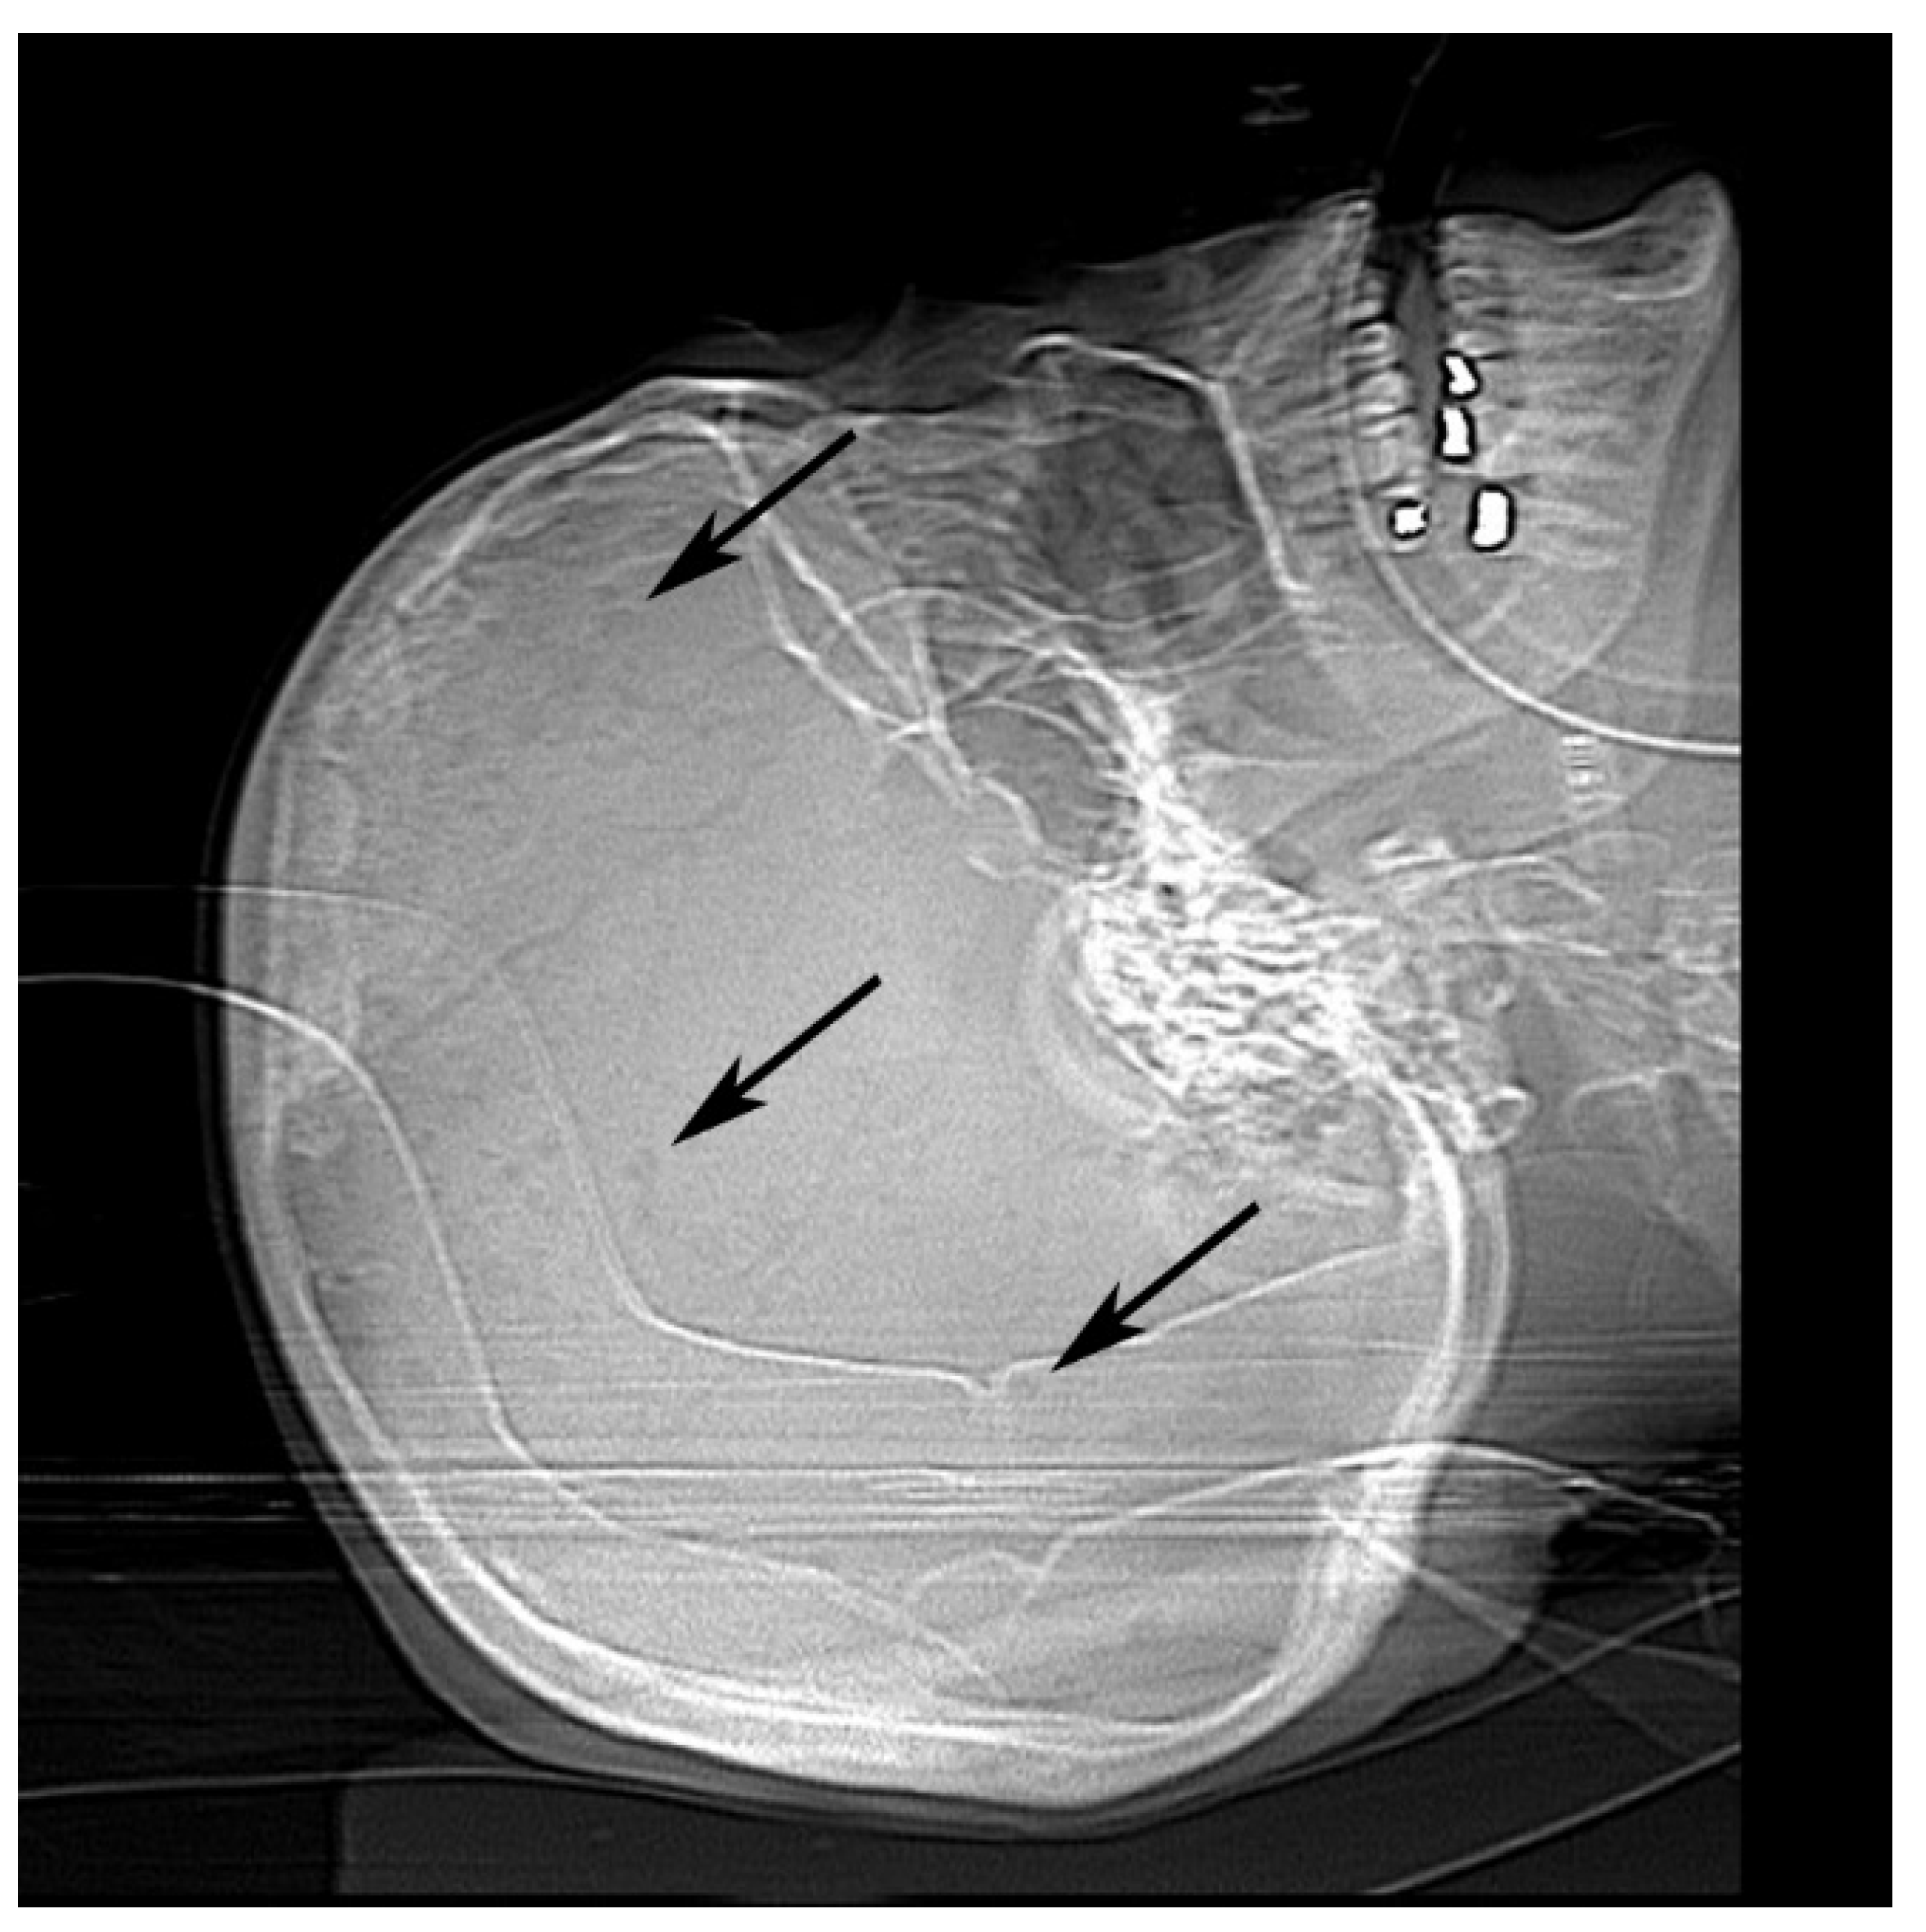

2.3. Autopsy Examination

2.3.1. Gross Findings